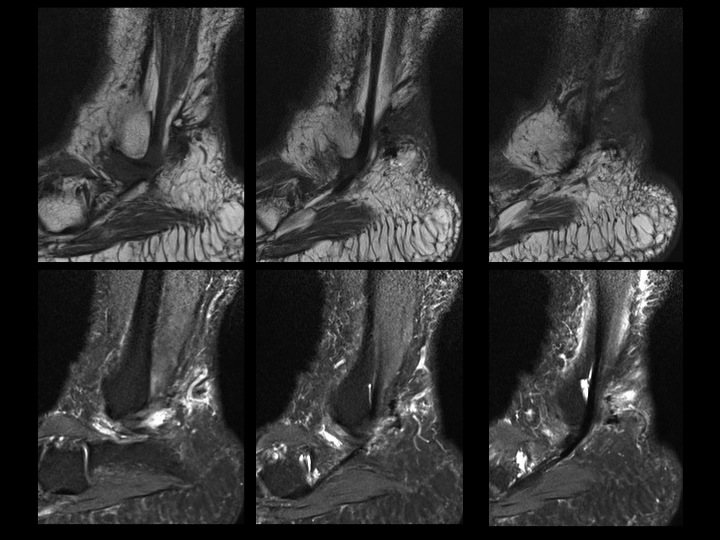

42 yr old female with 8 months burning lateral foot pain after ankle surgery

First 2 slides show an enormous os trigonum with posterior ankle impingement and associated FHL tenosynovitis. Latter 3 post op slides should extensive scarring obscuring fat planes in the region of the sural nerve which is presumably encased. Reference article.